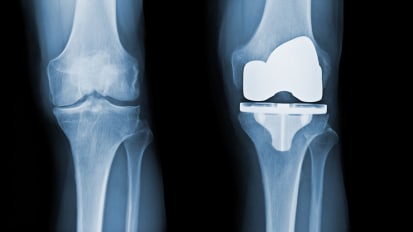

Can Total Joint Replacement Complication Rates Be Reduced?

Research by Johns Hopkins orthopaedic surgeon Savyasachi Thakkar suggests opportunities for safety and outcome improvements based on timing of multiple procedures.

Paradigm Shift: Patient Optimization Before Elective Arthroplasty

A recent review by Johns Hopkins orthopaedic surgeon Harpal Khanuja and colleagues found that it helps to give intravenous iron to patients who are very anemic, and in elective surgery cases, anemia should be treated before the patient has the procedure.

Better Blood Management Improves Patient Outcomes After Joint Replacement

Blood transfusions can increase the risk of adverse outcomes, delay rehabilitation and extend a patient’s hospital stay, so limiting blood loss is crucial.